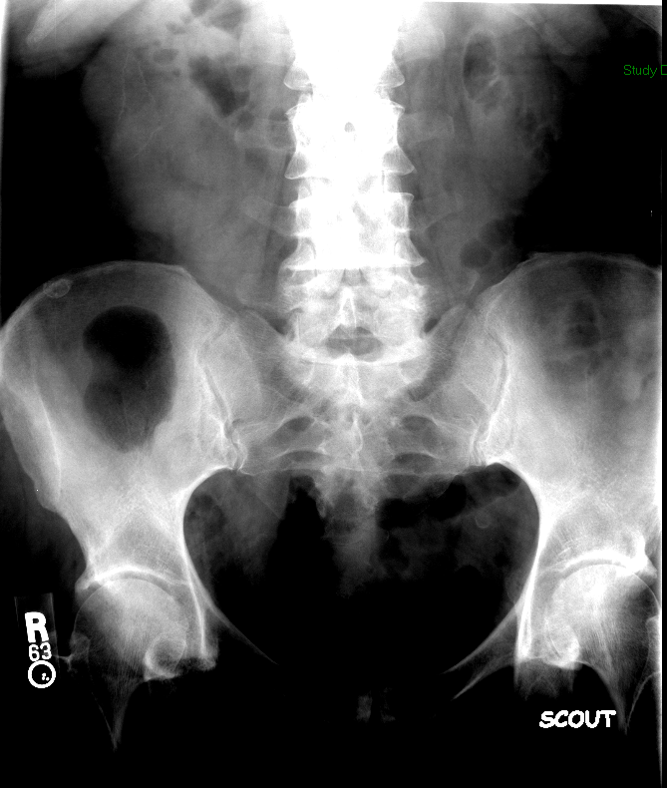

- With the patient seated on the defecography chair, obtain a scout image of the rectum and pelvis.

(key image 1). Be sure to include:

- the sacrum posteriorly

- the pubic symphysis anteriorly

- approximately 5cm below the skin surface of the perineum

- This extra room inferiorly will able you to view any prolapse that may occur without having to move the fluoro machine.

- the centimeter marker on the commode

- the barium-filled small bowel superiorly